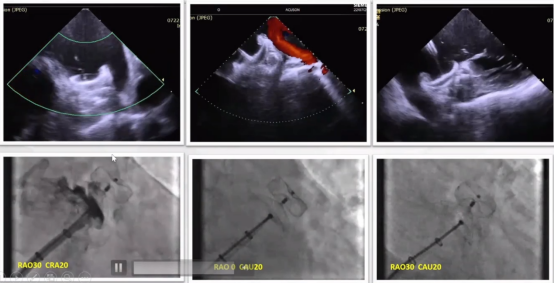

术中在ICE影像下,可以更清晰地验证封堵器位置及残余分流。

随后进行牵拉试验来验证固定盘的稳定性,使用DSA可辅助验证它的稳定性。

➪7.多角度评估残余分流

➪8.满足PAST原则,释放

释放后ICE导管回到右心室,再次评估残余分流,评估心包积液。